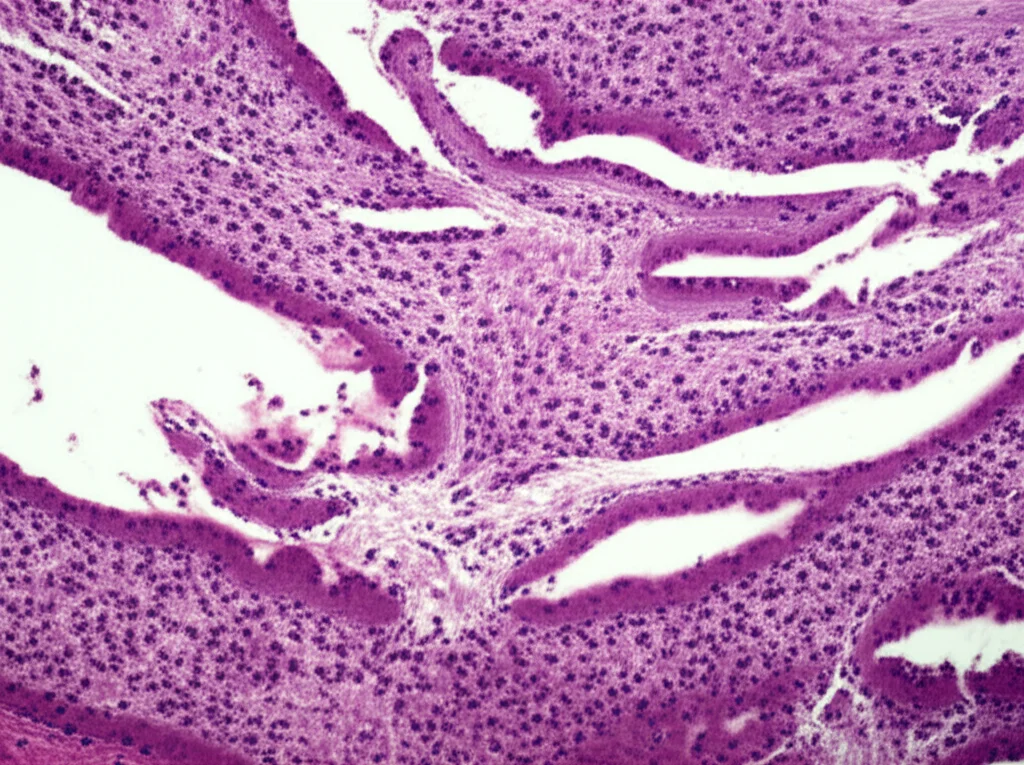

L’analisi istologica, cioè l’esame dei tessuti al microscopio, ha rivelato che nel gruppo di controllo c’era una fibrosi estesa (cioè tante cicatrici) e persino lipomatosi (accumulo di grasso) al centro dell’infarto. Un disastro. Invece, nei gruppi trattati con pASC e, soprattutto, nel gruppo cocultura, la cicatrice fibrotica era minima, sia al centro che ai bordi dell’area infartuata.

Ma la cosa più entusiasmante è stata vedere, tramite immunofluorescenza, che nei gruppi pASC e cocultura c’era espressione di α-actinina (una proteina fondamentale per la contrazione muscolare). E nel gruppo cocultura, abbiamo addirittura osservato la formazione di strutture sarcometriche, l’organizzazione base delle fibre muscolari cardiache, che erano completamente assenti nel gruppo di controllo! Era come se il tessuto stesse rinascendo!